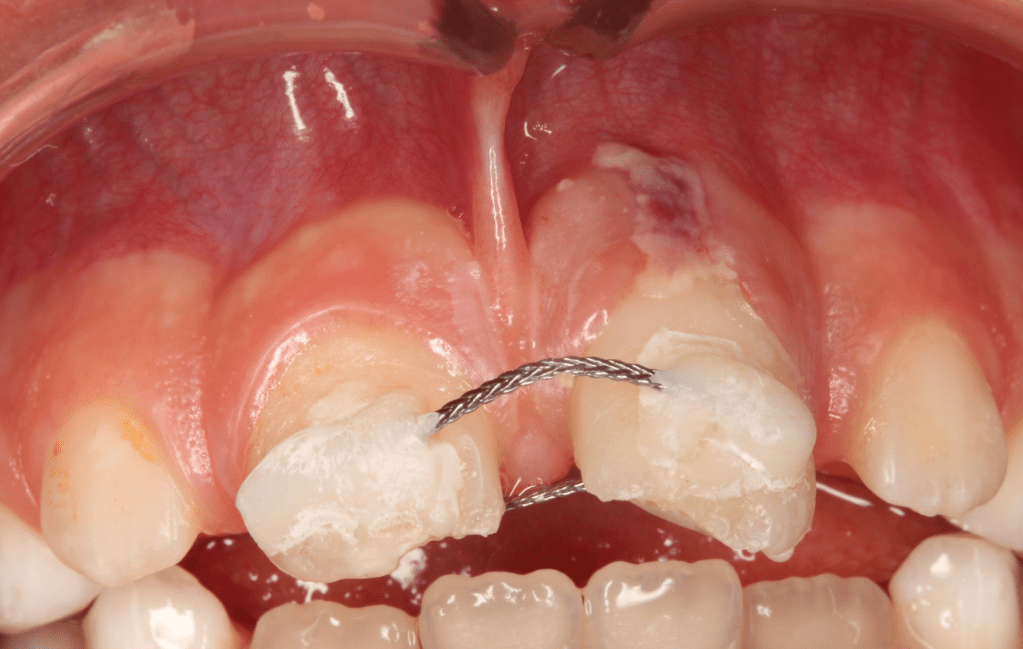

Fractura con exposición pulgar

Reconstrucción con recubrimiento pulgar indirecto